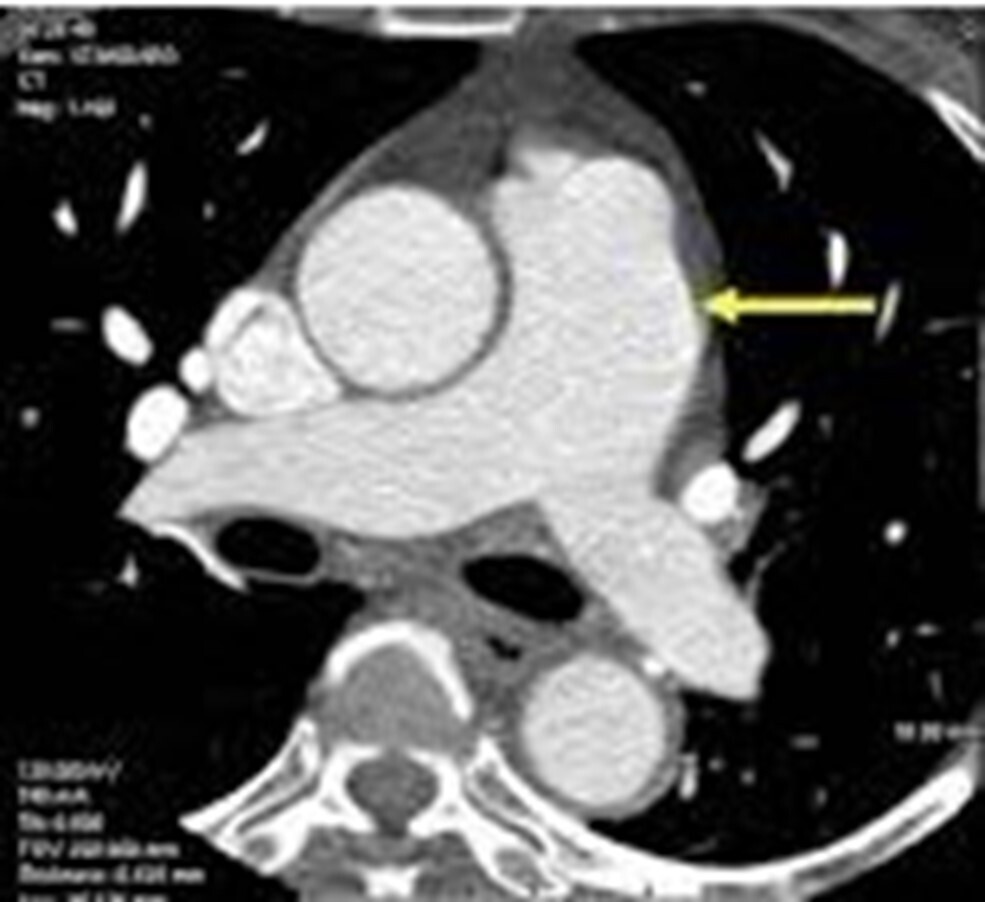

What aspects of the following image makes it so that the image has excellent enhancement?

A

-Contrast is in the pulmonary arteries only. There is very little contrast in the aorta

-64 slice scanner

-ROI was placed in the pulmonary artery and was triggered at 140 HU